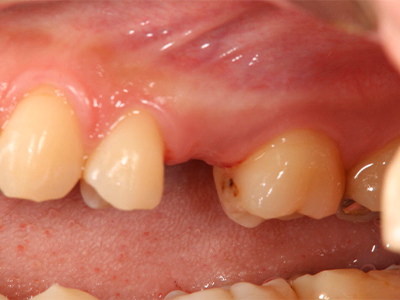

インプラント2歯欠損(臼歯)

治療前後写真

治療前

治療後

年齢・性別

47歳・女性

来院理由

左下の奥歯が痛くて咬めない

治療内容

- ① 抜歯後に診査・シミュレーション

- ② サージカルテンプレートを用い、インプラント埋入+歯槽骨造成を併用(一次手術)

- ③ 3ヶ月後に二次手術(歯肉移植併用)

- ④ 最終補綴装着→メンテナンス移行

治療期間

一次→二次手術まで約3ヶ月、その後最終補綴

費用

1,069,200円

リスク・副作用

口腔清掃・メンテ不足で周囲炎・感染・脱落の可能性

医院コメント

インプラント周囲に厚い角化歯肉を再建し、清掃性を高めて長期安定を図った。